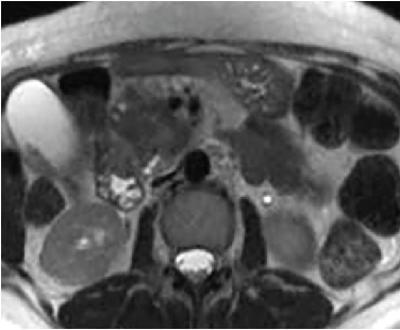

Shrinivas B. Desai, Ritu K. Kashikar, Shreya Shukla Radiological signs are classical and distinctive abnormalities characteristic of a disease. These can be seen on any imaging modality. Resemblance to commonly seen objects and patterns form the basis of radiological signs. The aim is to help the reader associate, understand and memorize these pathologies with the aid of signs. Various signs pertinent to hepatobiliary system are described in the chapter. Described on MRI when liver lesion shows a peripheral rim of high T2 signal intensity with the centre of the lesion appearing isointense to the background of noncirrhotic liver on T2WI mimicking an atoll. It is considered a characteristic sign of an inflammatory hepatic adenoma (image) but is only seen in about one-third of cases Extrinsic smooth impression over medial aspect of duodenum along its posteroinferior aspect, seen in pancreatic head pathologies like carcinoma. This sign is seen in pancreatic adenocarcinoma Presence of a persistently hyperattenuating dot within a lesion on arterial and portal venous CT. This corresponds with peripheral nodular enhancement seen on dynamic MR. Presence of bright dot suggests that the lesion is a hemangioma and helps in ruling out metastasis Ultrasound appearance of multiple cystic spaces or lesions that has been used to describe the appearance of an intraductal papillary mucinous neoplasm of the pancreas. Seen on contrast CT in portal hypertension. The appearance is based on resemblance to Medusa from Greek mythology. Dilated engorged paraumbilical veins radiating across umbilicus to join systemic veins is seen. This sign is seen in Caroli’s disease on contrast CT. Enhancing dots within dilated intrahepatic bile ducts represent portal radicles. Caroli’s disease Irregularly dilated pancreatic duct with multiple strictures and intervening dilatation with associated dilated side ductules resemble multiple lakes supplied by a single territory. Best seen in MRCP images. Chronic pancreatitis It is a finding on MRI and CT and is best seen on MRI T2-weighted and postcontrast T1-weighted sequences. Small necrotic/purulent areas in the pyogenic abscess ‘cluster’ together and then coalesce into a larger necrotic/purulent areas, eventually becoming a larger septated abscess cavity. At the periphery of these clusters: Associated with pyogenic hepatic abscesses and can help differentiate pyogenic abscesses from other types of liver lesions Abrupt termination of gas within the proximal colon at the level of radiological splenic flexure. The inflammatory exudates in pancreatitis extend to the phrenicocolic ligament giving rise to this sign Seen on grey scale ultrasound as a reverberation artifact when small calcific or highly reflective objects are imaged. The colour comet-tail artifact is an ultrasonographic sign seen in a number of situations when colour Doppler scanning is performed. This sign occurs in cases of traumatic right-sided diaphragmatic rupture with resultant partial herniation of liver through the defect. Separation of the herniated liver from its intra-abdominal component is via a small constriction at the level of diaphragm resembling a cottage loaf. Cottage loaf is a particular shape of bread in which larger and smaller roughly spherical balls are squashed together. Traumatic right-sided diaphragmatic rupture with resultant partial herniation of liver Bile eccentrically outlines luminal stone, creating a low attenuation crescent. Best seen on MRCP images. Choledocholithiasis Dilatation of both pancreatic duct and CBD is referred to as the double duct sign. Positive double duct sign suggests the diagnosis of carcinoma of the head of the pancreas and ampullary tumours and is hence considered ominous. Occasionally the sign may be seen in impacted gallstone in the distal duct. This feature is seen in patients with liver abscess on contrast-enhanced CT. A double, inner hyperattenuating and outer hypoattenuating rim is seen surrounding the hypodense abscess. The inner hyperattenuating rim corresponds to the enhancing abscess membrane, while the outer rim corresponds to the edema of the surrounding liver which appears hypodense and may show delayed enhancement. Liver abscess A positive duct penetrating sign is when a mass is penetrated by an unobstructed pancreatic duct; this makes focal pancreatitis the most likely cause rather than pancreatic carcinoma. This sign is best appreciated on MRCP (or ERCP). A radiographic sign that can be useful in differentiating between focal pancreatitis (inflammatory pancreatic mass) from pancreatic carcinoma. The duct-penetrating sign on MRCP is more helpful in differentiating between these two entities than a delayed enhancement pattern on CT or MRI It occurs when there is both limy bile and a gallstone in the common bile duct. The linear vertical radiopaque bile forms the line of the exclamation mark (i.e. !), whilst a more distal calculus forms the ‘dot’ at the end of the exclamation mark. Pathognomonic imaging sign of the rare diagnosis of limy bile on plain abdominal radiography Nonenhancing ruptured lesion with peripheral rim enhancement showing discontinuity from the rest of the liver and protruding from the liver surface is called the enucleation sign. Ruptured HCC Enlargement of the pericholecystic space. One of the signs of liver cirrhosis Can be seen on technetium 99m sulphur colloid scans of the liver and spleen, as well as CT studies. It occurs as a focal area of increased radiopharmaceutical uptake in the medial segment of the left hepatic lobe (segment IV) occurring as a result of SVC obstruction and portosystemic venous shunting between the superior vena cava and the left portal vein via the internal thoracic and paraumbilical veins. The equivalent of this sign may also be seen on contrast-enhanced CT scans as a hypervascular region. Budd–Chiari syndrome causes the hot spot sign in the caudate lobe

1) Atoll sign